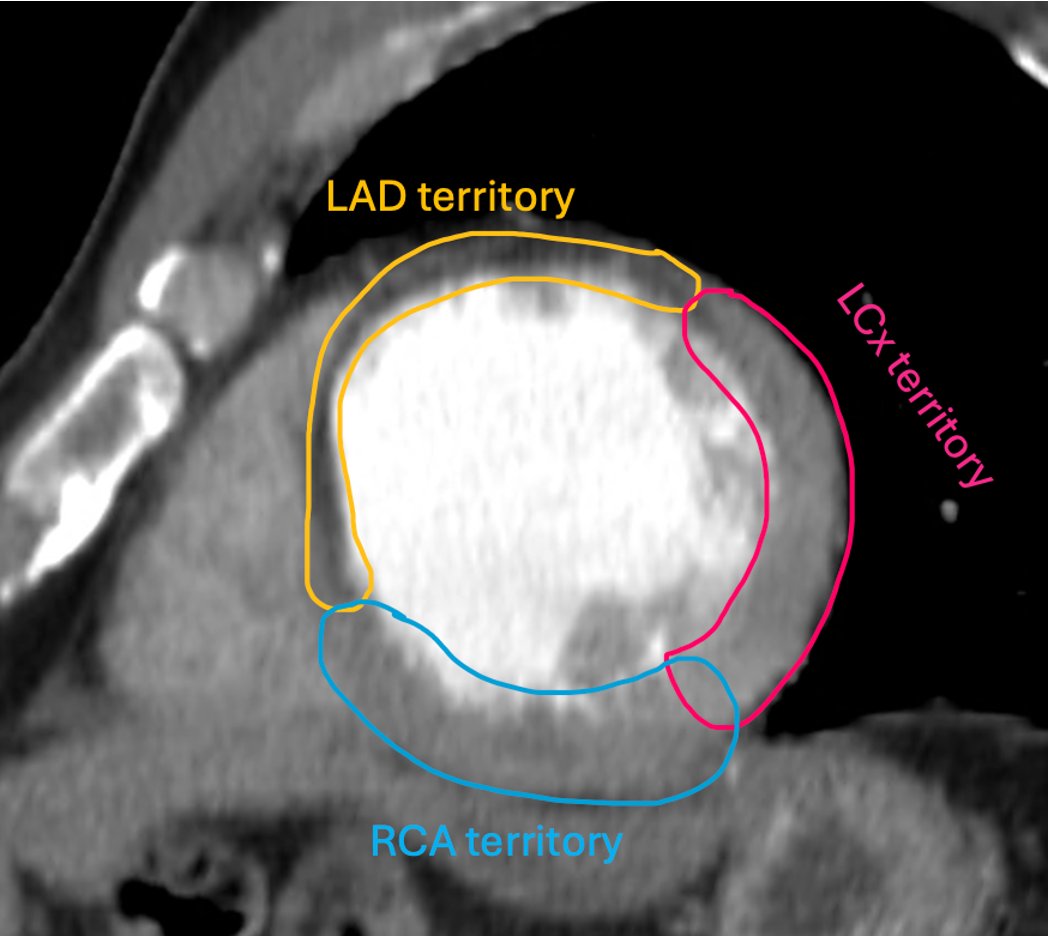

🫀💥 Answer: LAD occlusion Classic anterior wall / anteroseptal infarct pattern = LAD territory 🚨 Bonus points: proximal LAD if you’re seeing a big anterior + septal involvement. #RadTwitter #Cardiology #Radiology #MedTwitter #Radres

🫀⚡️ Unknown MI case Which coronary artery took this patient down? 👀 💥 Classic infarct pattern on imaging. 🎯 Name the culprit vessel! 👇 Drop your answer #RadTwitter #Cardiology #Radiology #MedTwitter #CCTA #Radres